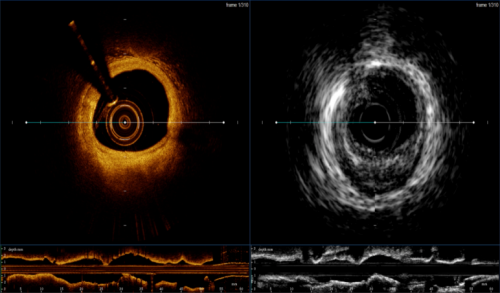

本次獲得注冊證的血管內(nèi)成像設備及導管是由全景恒升(Panovision)和哈爾濱醫(yī)科大學附屬第二醫(yī)院于波教授團隊共同研發(fā),這是一款將現(xiàn)有IVUS,OCT兩項技術(shù)融合的新一代腔內(nèi)影像機器及導管,產(chǎn)品擁有智能的算法平臺,突破性的探頭融合技術(shù)和優(yōu)異的圖像質(zhì)量,提供一系列多模態(tài)的成像方式和臨床診斷影像學解決方案,旨在幫助術(shù)者全面準確獲取管腔IVUS,OCT信息,助力術(shù)者實現(xiàn)精準醫(yī)療。

S1配備手動和自動測量管腔面積、直徑、長度且提供智能支架和管腔輔助探測功能,輔助分析支架貼壁不良,專業(yè)直觀的軟件界面設計,實現(xiàn)各種功能一鍵切換,盡享絲滑;配備三種類型的成像模式,醫(yī)師可選擇IVUS,OCT雙模水平視圖或重疊融合視圖,也可選擇單模成像,此外血管三維重建體渲染技術(shù)提供了360度全方位觀察視角并且可多角度旋轉(zhuǎn)拉伸,讓臨床醫(yī)師從多維度觀察病變。

本次獲批產(chǎn)品配備三種成像導管(C1-1二合一導管,C2-1 IVUS導管,C3-1 OCT導管);多種成像速率和回撤速度可實現(xiàn)醫(yī)師臨床中實時調(diào)節(jié),成像速率為20幀/秒-200幀/秒,回撤速度別為1mm/s-40mm/s;回撤最長距離為150mm保證縱向測量需求。

作為冠狀動脈介入診療中最主要的兩種血管腔內(nèi)影像學技術(shù),兩種影像學技術(shù)已成為心血管介入醫(yī)生不可或缺的輔助手段,其自身都有一定的優(yōu)勢和缺陷,OCT具有更高的分辨率,能更好地分析斑塊成分,但是穿透深度有限;IVUS具有更強的穿透力,能夠更深層的成像,但空間分辨率較弱。

也正是因為如此,將二者合一才能幫助醫(yī)師全面準確獲取管腔信息,精準實現(xiàn)高質(zhì)量PCI。